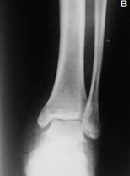

Post Traumatic Anterior Sub-talarDislocation

Grimi Talal*, Benhazem Omar, Ouazzani Nabil, Fekhaoui Med Reda, Bouya Ayoub, BoufetalMoncef, El Bardouni Ahmed, Berrada Mohammed Saleh